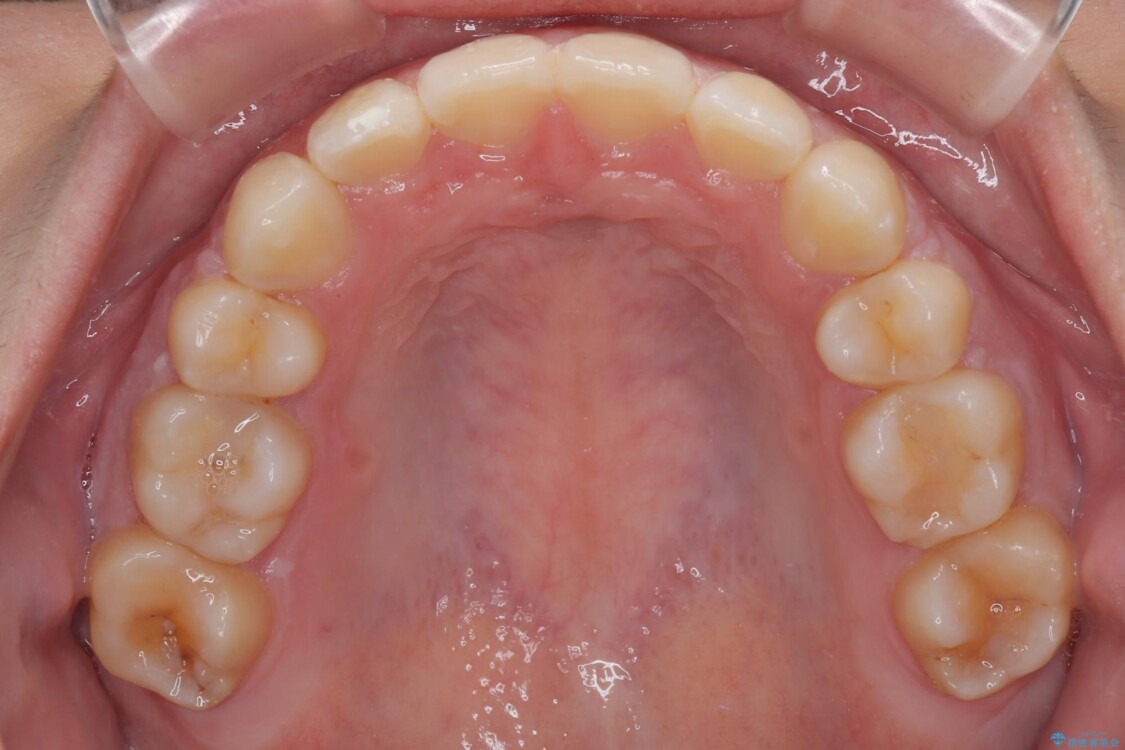

治療途中

• 転勤でも安心して治療継続 抜歯スペース閉鎖と深い噛み合わせ改善のワイヤー矯正 治療途中画像